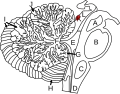

Inferior colliculus (K) from a cerebellar perspective. Sagittal view.

Inferior colliculus (K) from a cerebellar perspective. Sagittal view. -